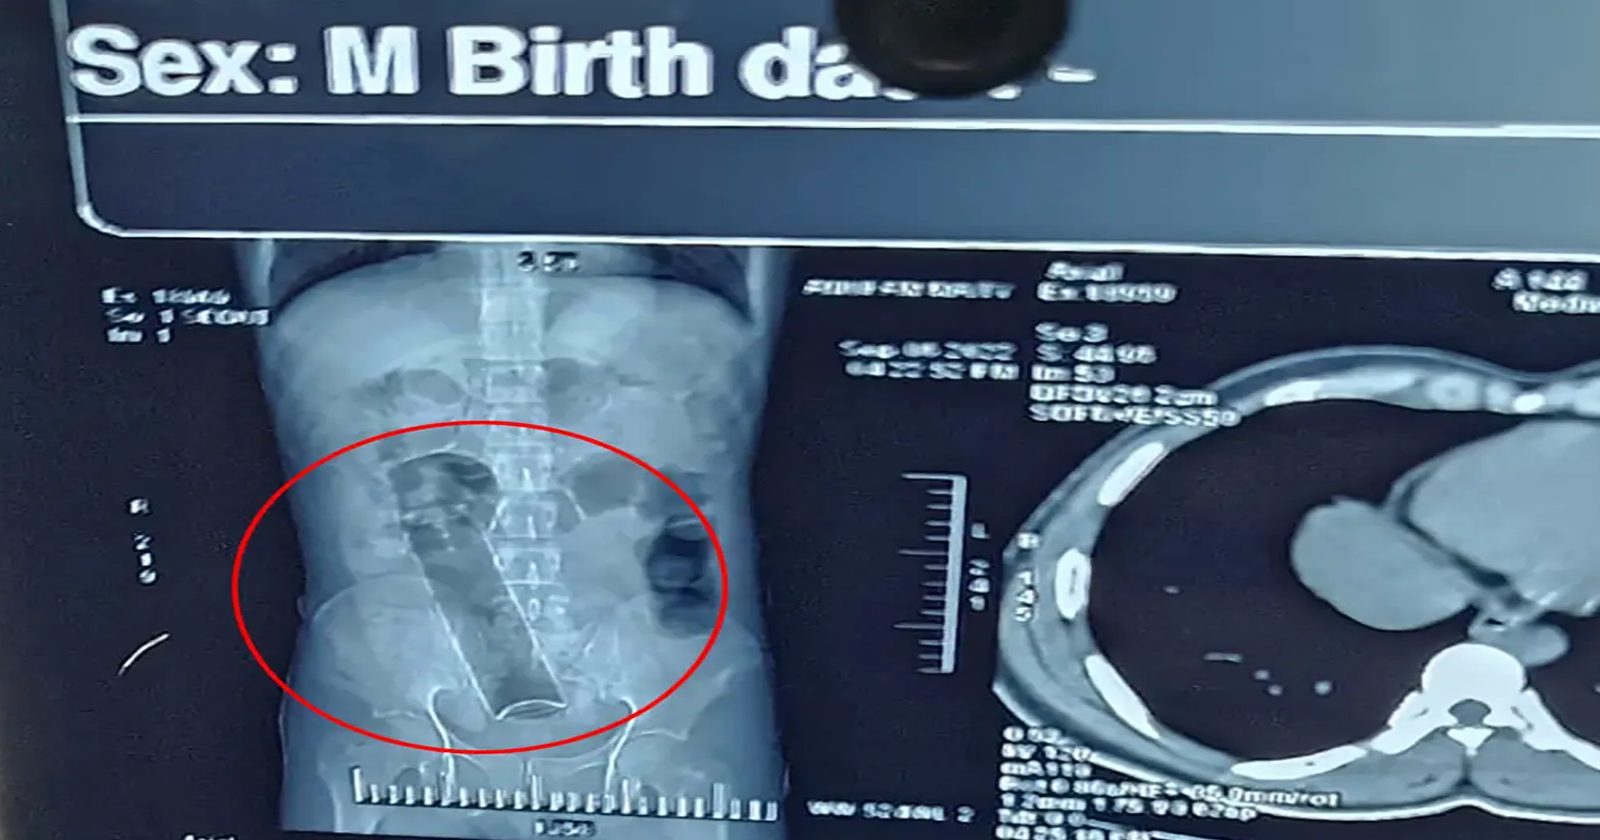

ووفقاً لما كتبه الأطباء، فقد كان الشاب يعاني من ألم شديد لدرجة أنه لم يتمكن من الخضوع لفحص المستقيم، مما أجبر المسعفين على الاعتماد على الأشعة السينية للعثور على المكان الذي ذهبت إليه العلبة.

وتم بعد ذلك نقل الشاب إلى غرفة العمليات في قسم الطوارئ بجامعة طهران للعلوم الطبية، حيث قام الجراحون بفتح في بطنه وأزالوا العلبة في نفس اليوم.